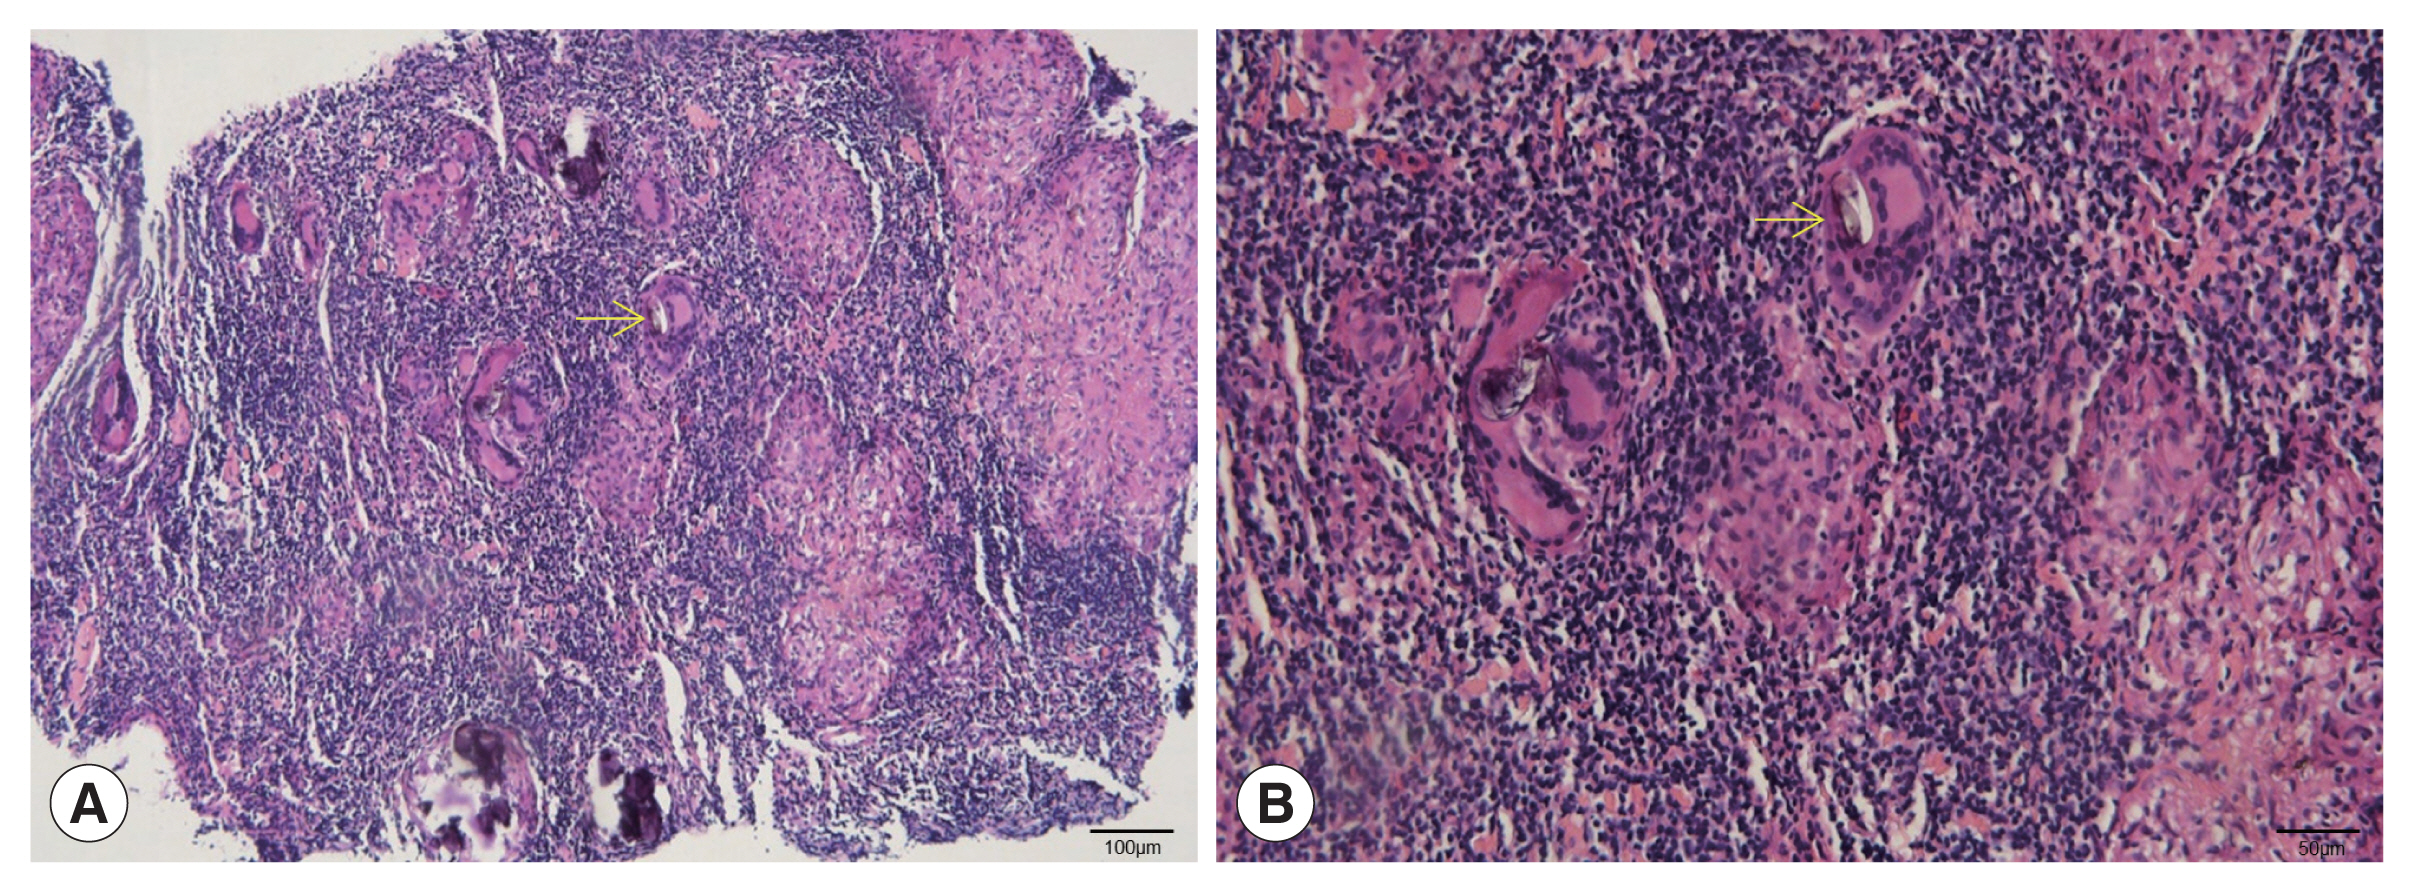

The patient was a 53-year-old woman living in Hefei City (Anhui Province). She was admitted to our department in 2022 with a small mass in the right armpit that had been persisted for over 1 month. The patient had no fever and no inflammatory manifestations in the right armpit. She had not experienced fever, chills, night sweats, or gastrointestinal, musculoskeletal, or neurologic symptoms. Her physical examination revealed a mass in the right armpit, approximately 4.0 cm×2.0 cm×1.0 cm in size. Breath sounds were normal. Complete blood counts showed a normal level of eosinophils (0.11×109/L), while red blood cell (3.66×1012/L), and hemoglobin (113 g/L). Hematocrit (0.332 L/L) levels were below the reference range. Blood coagulation functions were within the normal range. Ultrasonography of the liver, breast, thyroid gland, cervical lymph node, and inguinal lymph nodes revealed no specific lesions. Ultrasonography of the right axillary lymph nodes revealed more than 3 hypoechoic oval shaped nodules that had a clear edge. Strong-echo light spots were diffusely distributed in the hypoechoic nodules, the largest of which was 41 mm×17 mm (Fig. 1A). Color doppler ultrasonography showed that the dot-bar color doppler flow signal was relatively rich in these enlarged hypoechoic nodules (Fig. 1B). Histological examination of biopsy samples from the right axillary lymph nodes revealed granulomas containing multinucleated giant cells and elliptic calcified Schistosoma eggs (Fig. 2). In further questioning, the patient stated that 7 years prior to symptom onset, she had travelled through Yunnan province, where she had spent sometimes swimming in Lake Erhai, an endemic area for Schistosoma japonicum.

Schistosomiasis of the axillary lymph nodes has rarely been reported. Our patient had no clinical symptom, but an axillary mass was confirmed by histopathological examination. Schistosoma eggs could be differentiated from those of Paragonimus and Fasciola by their shape, which was elliptic, and their eggshell thickness, which was uniformly distributed. The Paragonimus egg is ovoid, unembryonated, and thick-shelled, with an operculum at one end and opercular shoulders; similarly, the Fasciola egg is ovoid, unembryonated, large, and operculated. However, the Schistosoma egg is embryonated and do not have an operculum. The main ultrasonographic manifestations were lymphadenectasis and calcification, and the calcification pattern was the same as lymphoid reactive hyperplasia [6]. Ectopic schistosomiasis should be differentiated if there are ultrasound findings of lymphangiectasia and calcification in the lymph nodes in patients who have traveled to schistosomiasis endemic areas or have been in potentially contaminated water. The definitive diagnosis should be carried out by fecal egg examination and ultrasound-guided histological examination.